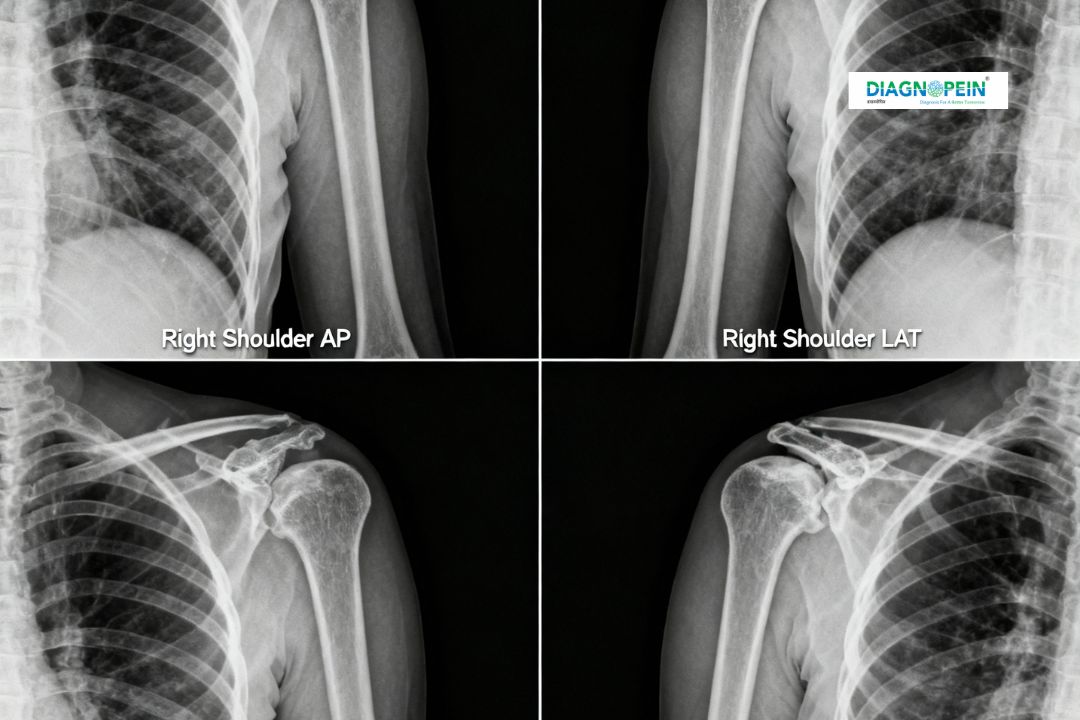

An X-Ray Both Shoulder AP/LAT (Right & Left) is a specialized radiographic imaging test that provides detailed views of both shoulder joints. The terms AP (Anteroposterior) and LAT (Lateral) refer to the two standard views captured to examine bones, joint spaces, and surrounding structures. At Diagnopein in Karad, this test helps detect shoulder injuries, joint abnormalities, fractures, and other musculoskeletal conditions effectively.

The shoulder joint is one of the most mobile joints in the body, making it prone to injuries and wear. Performing an X-Ray Both Shoulder AP/LAT RT & LT helps doctors assess both shoulders for symmetry, bone alignment, and underlying issues that may not be visible externally.

Parameters Evaluated During X-Ray Both Shoulder AP/LAT

During the test, several anatomical and structural parameters are carefully observed to provide a thorough report.

Evaluated Parameters:

1. Shoulder bone alignment and contour

2. Joint space width and symmetry

3. Clavicle and scapula structure

4. Presence of fractures, lesions, or degenerative changes

5. Any abnormalities in surrounding soft tissue or joint margins

These diagnostic insights help doctors provide accurate treatment for injuries, chronic inflammation, or degenerative bone diseases.